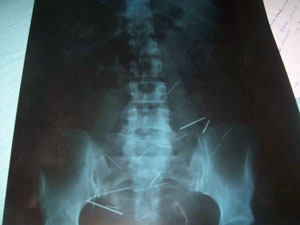

De acordo com o médico, a paciente passa bem, mas aguarda em casa uma vaga no Hospital Regional de Santarém, para uma nova avaliação do caso. Em Santarém, a equipe médica vai avaliar a necessidade de uma intervenção cirúrgica.

O clínico geral Lourival Leonel de Souza, do Hospital Municipal de Monte Alegre, disse ao G1 que a paciente procurou atendimento se queixando de dores no ouvido. “Ela foi medicada com analgésico, mas horas depois surgiu um novo quadro, de fortes dores na região da bacia. A paciente não conseguia nem andar.” Ainda segundo o clínico, a mulher foi medicada e melhorou.

O médico afirmou que a mulher disse que introduzia as agulhas no corpo quando tinha entre 9 e 10 anos. Sua mãe era costureira, por isso ela tinha fácil acesso aos objetos em casa.